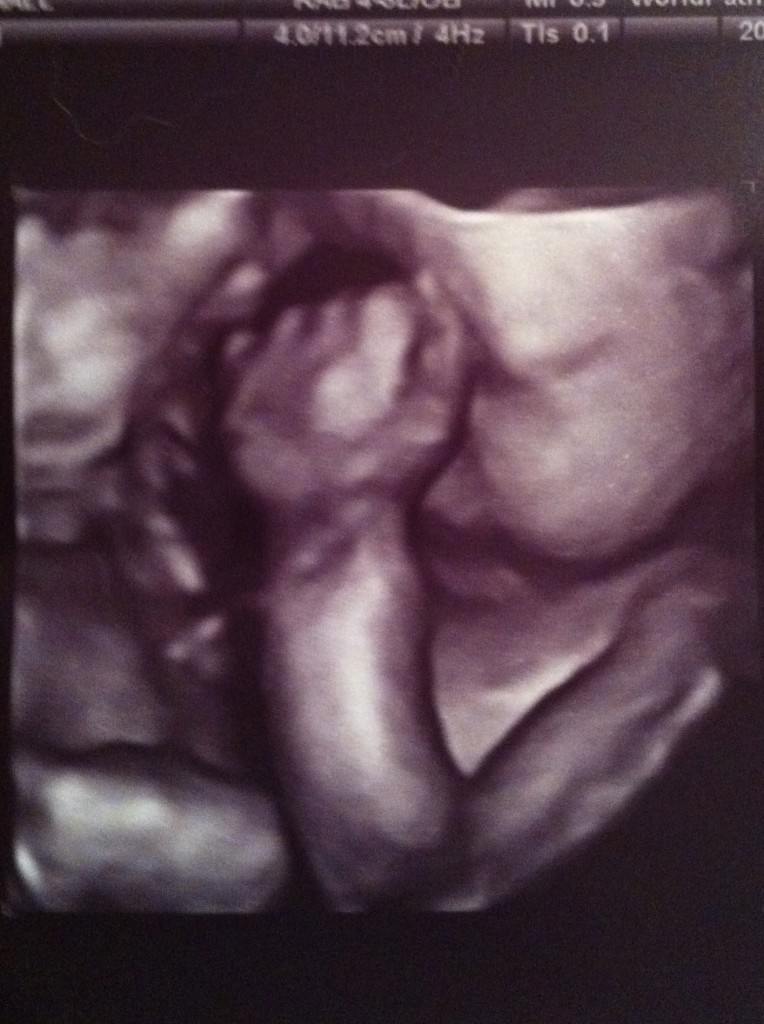

Skip ahead to now… we are just over 3o weeks. Our wonderful doctor moved clinics, and due to the exorbitant prices of the new clinic, we needed to find a new doctor. I saw one at our original clinic but she was just not the right fit for us. We made an appointment with Dr. Kong, who comes highly recommended from many friends here (she’s delivered just about every SCIS Pudong baby in the last 10+ years). We had our first appointment yesterday and LOVED her, our midwife, and the nurses. SO thankful, as changing doctors during our first pregnancy, in a foreign country, this late in the pregnancy was a fairly large source of stress. That stress melted away within minutes of walking into our appointment. As if loving our new caretakers wasn’t enough, we were treated to these INCREDIBLE 4D ultrasound photos of our Isla…

I cannot get over how beautiful she is! I love those chubby little cheeks already!!! My eyes welled with tears throughout the ultrasound… so, so thankful! Everything felt so much more real once we saw her little face. Our sonographer excitedly jumped up and down, announcing that Isla has lots of long hair! I couldn’t believe it. She focused on the top of her head and showed us the hair. Additionally, Isla is “head down” (hooray!), weighs 1.6kg, and right on track. Mommy, however, was diagnosed with gestational diabetes a few weeks earlier (boo!), but we suspect this is due to my indulgence of evil (but yummy) foods at home over the summer. Got my diabetes test and will now be monitoring my blood sugar 4 times a day. Not the most fun, but worth it to ensure our little pumpkin is healthy.